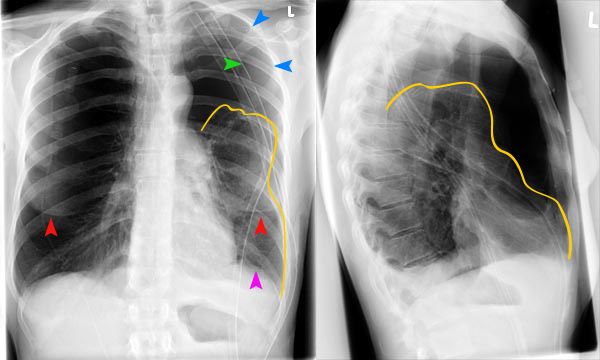

- рентген легких в двух проекциях: фронтальной и боковой;

При перкуссии отмечается ослабление перкуторного звука, причем верхняя граница представляет собой косую линию-Дамуазо, которая хороша видна на рентгенографии. При выслушивании легких фонендоскопом отчетливо слышен шум трения плевры, он похож на скрип снега. Дыхание в местах скопления жидкости резко ослаблено.

На рентгенографии симптомы выпотного плеврита легких отображаются как интенсивное однородное затемнение в нижних долях органа. Высокое стояние диафрагмы наблюдается при небольшом скоплении жидкости. Средостение смещено к здоровому легкому. При выполнении снимка в латеропозиции (больной ложится на бок) происходит горизонтальное смещение экссудата.

Не выпотной плеврит легких на снимке проявляется интенсивными тенями неоднородной структуры, синусы не определяются. Подвижность плевры резко ограничена.